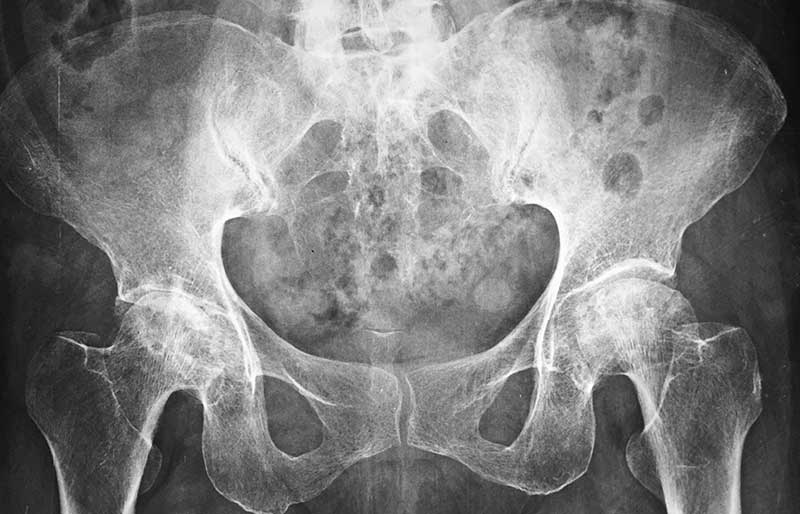

Operasi penggantian sendi panggul adalah suatu operasi untuk mengganti sendi panggul yang rusak dengan sendi buatan yang disebut prosthesis. Penyebab utama kerusakan sendi panggul adalah osteoartritis (baca penjelasan tentang “Osteoartritis”) dan sendi panggul adalah sendi terbanyak kedua setelah lutut yang terserang penyakit ini.